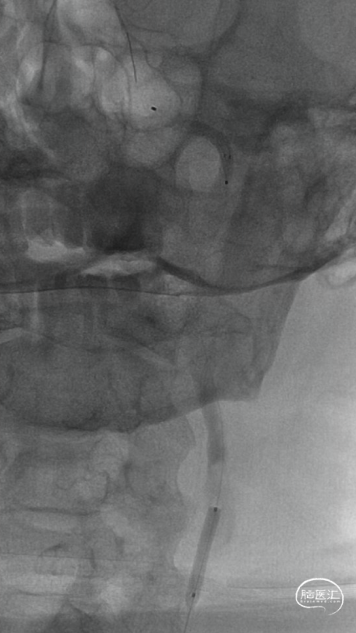

微导管微导丝配合下多次尝试通过颈内动脉起始部闭塞段未能成功,在125mm多功能导管配合下,将微导管及Command微导丝成功越过颈内动脉起始部闭塞段,微导管造影确认在颈内动脉真腔,但远端未见显影,考虑血栓所致。静脉推注替罗非班8ml,并以6ml/h持续泵入。

交换出微导管及多功能导管,C2段放置SPIDER保护伞后以3-30mm球囊和6F 115cm SKATHI远端通路导管采用球囊接力技术越过颈内动脉闭塞段,由下及上持续抽吸。

抽吸状态下整体撤出保护伞,继续抽吸,血栓堵塞SKATHI导管及导引导管,负压下整体将系统撤出,可见大量血栓。